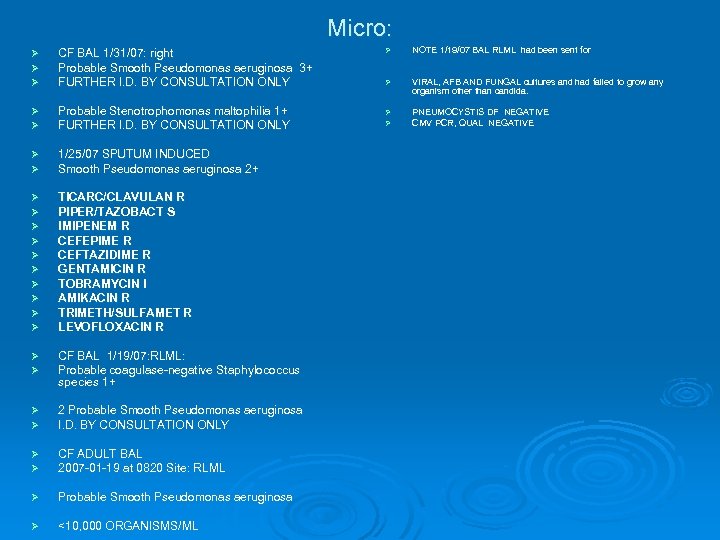

Micro: Ø Ø Ø CF BAL 1/31/07: right Probable Smooth Pseudomonas aeruginosa 3+ FURTHER I. D. BY CONSULTATION ONLY Ø Ø Probable Stenotrophomonas maltophilia 1+ FURTHER I. D. BY CONSULTATION ONLY Ø Ø 1/25/07 SPUTUM INDUCED Smooth Pseudomonas aeruginosa 2+ Ø Ø Ø Ø Ø TICARC/CLAVULAN R PIPER/TAZOBACT S IMIPENEM R CEFEPIME R CEFTAZIDIME R GENTAMICIN R TOBRAMYCIN I AMIKACIN R TRIMETH/SULFAMET R LEVOFLOXACIN R Ø Ø CF BAL 1/19/07: RLML: Probable coagulase-negative Staphylococcus coagulase-negative species 1+ Ø Ø 2 Probable Smooth Pseudomonas aeruginosa I. D. BY CONSULTATION ONLY Ø Ø CF ADULT BAL 2007 -01 -19 at 0820 Site: RLML Ø Probable Smooth Pseudomonas aeruginosa Ø <10, 000 ORGANISMS/ML Ø NOTE 1/19/07 BAL RLML had been sent for Ø VIRAL, AFB AND FUNGAL cultures and had failed to grow any organism other than candida. Ø Ø PNEUMOCYSTIS DF NEGATIVE CMV PCR, QUAL NEGATIVE